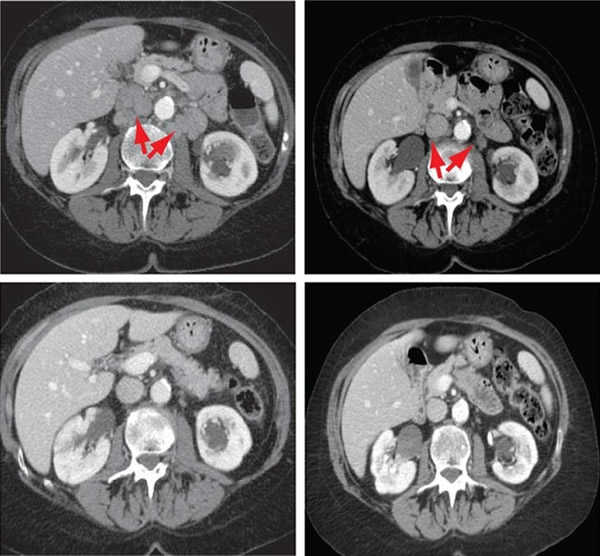

这个膀胱癌患者的转移瘤在服用了一种试验药物后消失了

美国纽约市纪念斯隆—凯特琳癌症中心(MSKCC)的研究人员,对于一位转移性膀胱癌女患者在接受了一种名为依维莫司的药物治疗后肿瘤全消的案例感到困惑不解——这种药物的靶点是参与细胞生长的被称为mTORC1的蛋白质。依维莫司对于临床试验中的大多数人都没有作用,并且作为单一的膀胱癌治疗药物已经被放弃。然而MSKCC及纽约市维尔康奈尔医学院的内科学家David Solit指出,这位患者在两年半的时间里都没有患上癌症——对于这种耐受化疗的癌症而言,这是一个“史无前例的漂亮结果”。